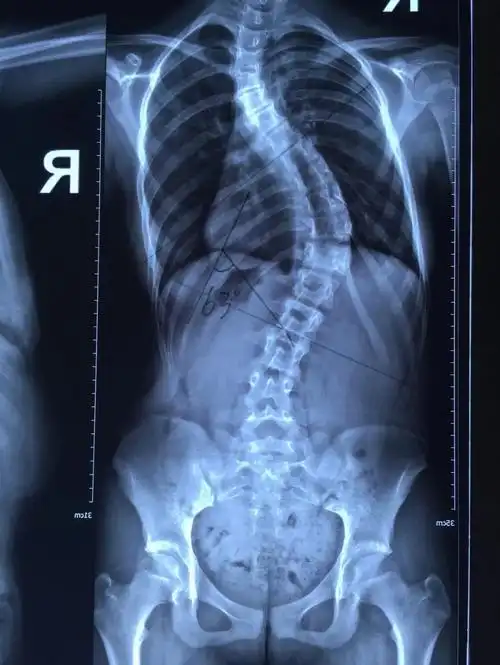

脊柱侧弯,影响儿童健康的大"杀手"75 72《"健 - 抖音

[精] 脊柱弯曲,你叫我如何有个美好的童年!

脊柱侧弯篇

新苗脊柱侧弯医体治疗体系4060度治疗好转的病例